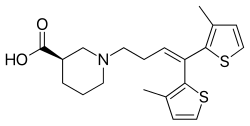

Farmacológico

La terapia “clásica” que se realiza en más del 90 % de todos los enfermos epilépticos es a través de medicamentos inhibitorios de crisis: los antiepilépticos. Normalmente esta terapia medicamentosa se realiza a lo largo de muchos años. Gracias a ello muchos de los pacientes tratados (un 60 % aproximadamente) reducen de manera importante la frecuencia de las crisis y en más del 20 % de los casos se consigue alguna mejora. La tolerancia de los fármacos antiepilépticos (AED, por sus siglas en inglés) no es muy buena en general. En algunos casos, estos medicamentos pueden tener efectos secundarios adversos debido a la alta dosis requerida para el control de las crisis, siendo absolutamente necesaria una vigilancia facultativa regular de la terapia. Los efectos secundarios pueden ser agudos (reacción alérgica cutánea) o crónicos (vértigo, letargo, náuseas, alteraciones del comportamiento...).[35]

Además, se calcula que la respuesta a los fármacos puede estar condicionada hasta en un 85 % por factores genéticos, por lo que ya existen en el mercado pruebas que recogen la información farmacogenética del paciente para que el médico pueda valorar qué tratamiento va a funcionar mejor en el paciente con epilepsia, en función de sus características genéticas. Así el médico puede escoger el tipo de fármaco y la dosis más adecuada que evite al máximo posible los efectos secundarios.[36]

El fármaco antiepiléptico concreto debe ser individualizado en función del síndrome epiléptico, tipo de crisis, edad del paciente, otras patologías que sufra el paciente, interacción con otros medicamentos, características específicas del paciente (mujer en edad gestacional, embarazo, peso, etc.) y preferencias del paciente (perfil de efectos secundarios, número de tomas al día, etc.).[35]